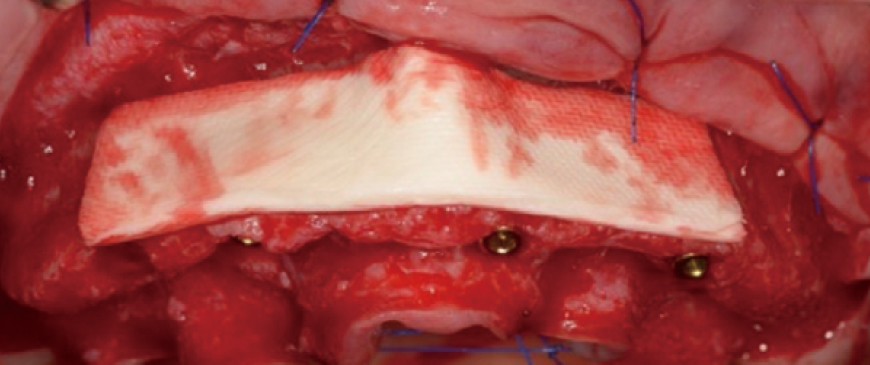

Fig 5

Ossix Volumax was used to create the contourization. This material ensures the desiredvolume and contour in the implant area. by performing the surgery in a simple manner, the chance of early complications caused by the surgery is almost eliminated.

Fig 6

Since only minimal augmentation (contourization) was performed using Ossix Volumax, the suturing could be done easily and simply without the need for a separate periosteal releasing incision.